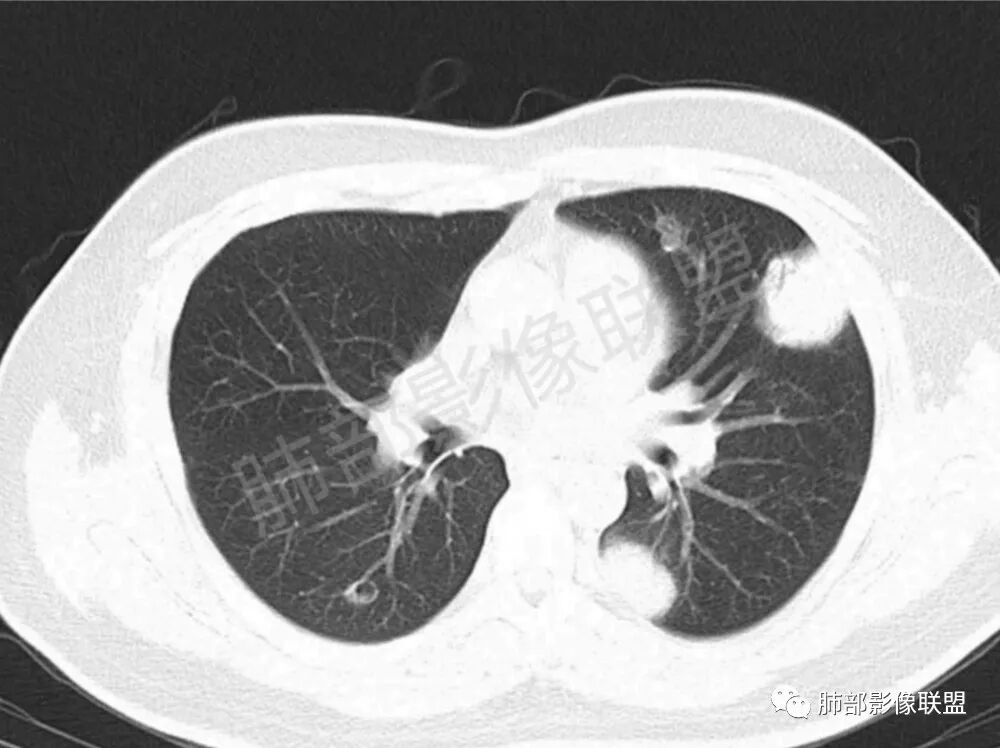

男性,22岁,HIV病史,症状半年,双肺多发大小不等结节影,边缘光滑,密度均匀,以胸膜下分布为主,部分与胸膜相连,胸膜下脂肪间隙可见,病灶近段支气管走行病灶内,远端似有堵塞,无增强图像,考虑隐球菌,鉴别:淋巴瘤,GPA

双肺多发结节影,膨隆,边缘光滑,圆顿,沿支气管血管束分布为主,部分贴胸膜,部分见空洞,空气支气管征

两肺多发结节性,大部分位于胸膜下,部分结节周围可见晕征。局部结节内可见扩张的支气管,纵隔淋巴结大,脾大,22岁男,HIV阳性,常规先考虑隐球菌。鉴别淋巴瘤,结核,马儿。

男,22,半年前咳嗽伴少痰,查HIV阳性,痰查TB阳性,既往有肺部斑片影伴空洞、纵隔淋巴结肿大、脾大。SCC、CA50、CA199、FER增高,此次胸部CT:两肺多发结节影,部分沿血管束分布,部分贴胸膜下,大小不一,密度不一,部分较散、边缘模糊,部分较实、圆钝、周围模糊晕,部分结节有支气管进入穿行自然,部分结节有血管分支自如通过。考虑HI∨相关淋巴增殖类病变,淋巴瘤?LYG?鉴别PC、TB。

青年男性,半年前咳嗽,HIV阳性,结核DNA阳性,肿标糖类抗原和铁蛋白增高。外院影像有纵隔淋巴结增大伴脾大,肺部病灶空洞。现在影像:肺内多发沿支气管分布(有支气管充气征,长轴沿支气管分布)及胸膜下分布(平行于胸膜)的大小不等结节,个别伴有空洞,双侧腋窝淋巴结肿大。纵隔图片不够,是否还有淋巴结肿大未知,脾脏未显示。

1.双肺多发大小不一结节,外围为主,边界尚清,部分周围似有GGO

2.类圆形,部分与胸膜相连,糊墙

3.支气管通畅或近端堵塞

空洞  游走  多变  支气管血管束分布,好符合啊

影像学缺乏特征性,以支气管血管周围、胸膜下及双肺下叶周边多发结节影最多见,结节易坏死形成空洞,伴有游走性和多变性的特征,结节周围可有磨玻璃样晕征,有时也可见单发结节影、薄壁的囊状阴影或弥漫性浸润影。肺门、纵隔淋巴结肿大少见, 可见胸腔积液和气胸。

结节型∶表现为两肺多发大小不等的结节,以两肺中下野多见,结节边缘欠锐利;